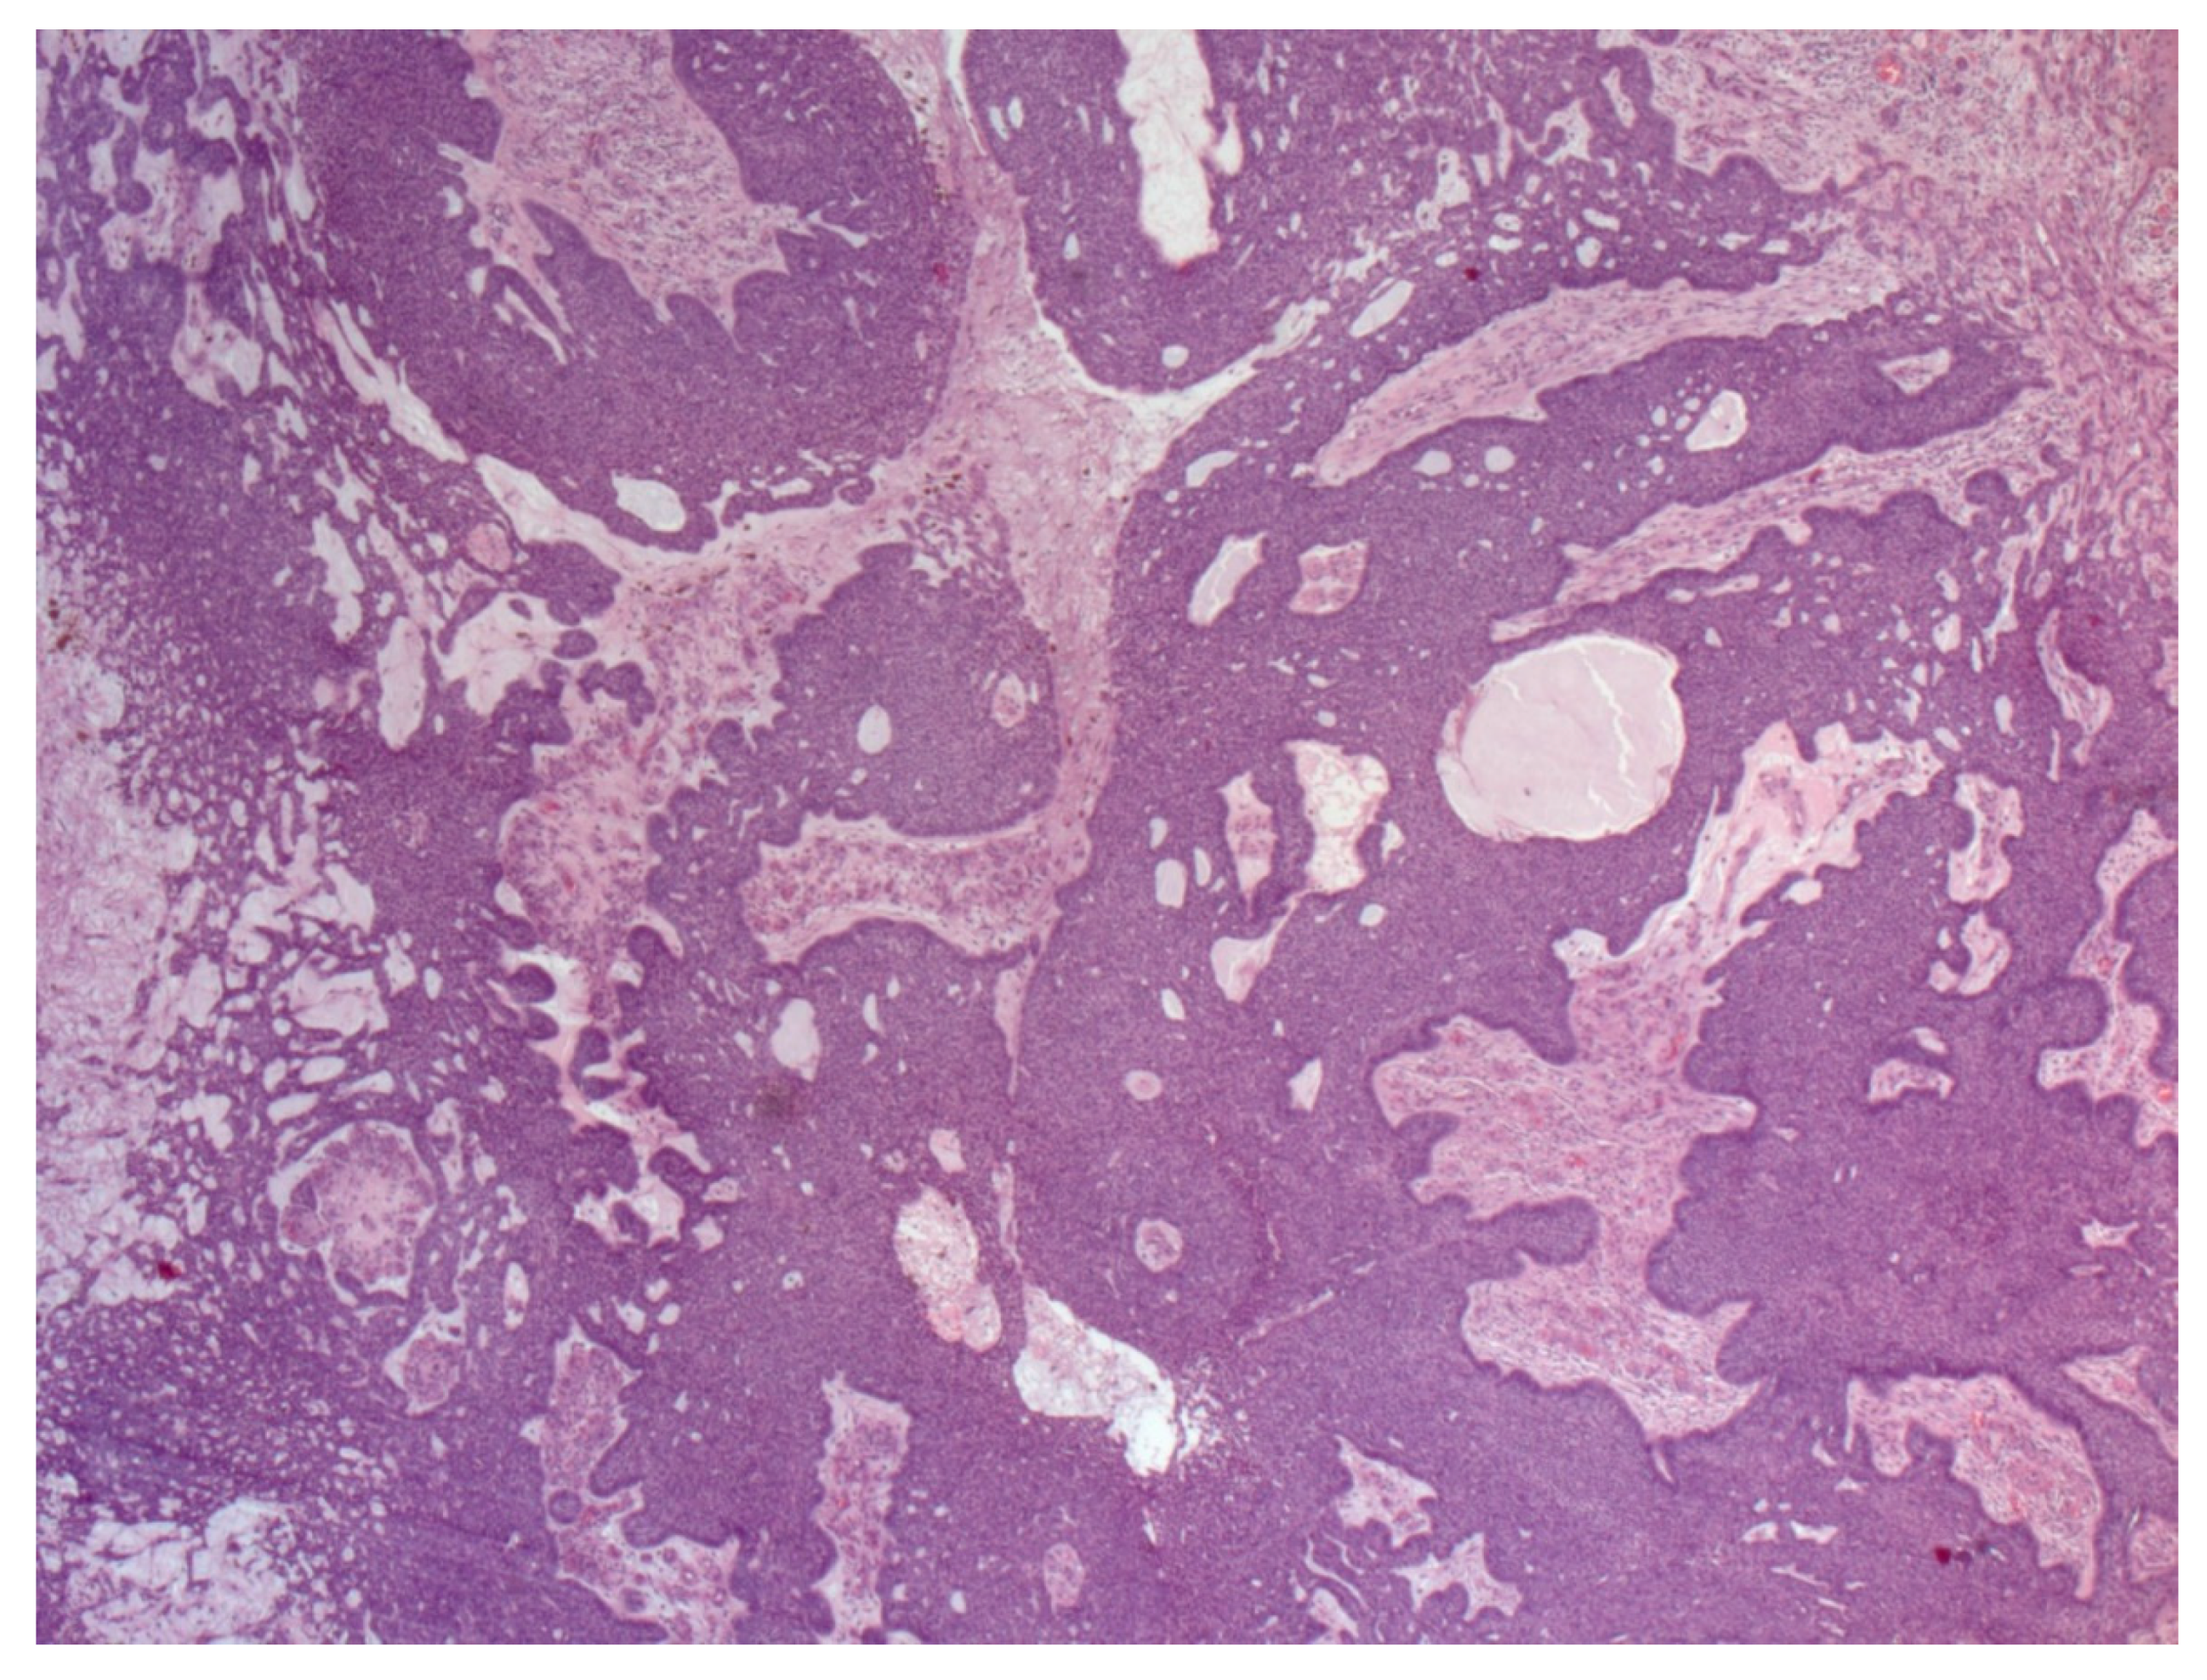

4. Histopathological Features of BCC

- Paolino, G.; Donati, M.; Didona, D.; Mercuri, S.R.; Cantisani, C. Histology of Non-Melanoma Skin Cancers: An Update. Biomedicines 2017, 5, 71. [Google Scholar] [CrossRef]

- Crowson, A.N. Basal cell carcinoma: Biology, morphology and clinical implications. Mod. Pathol. 2006, 19 (Suppl. 2), S127–S147. [Google Scholar] [CrossRef] [PubMed]